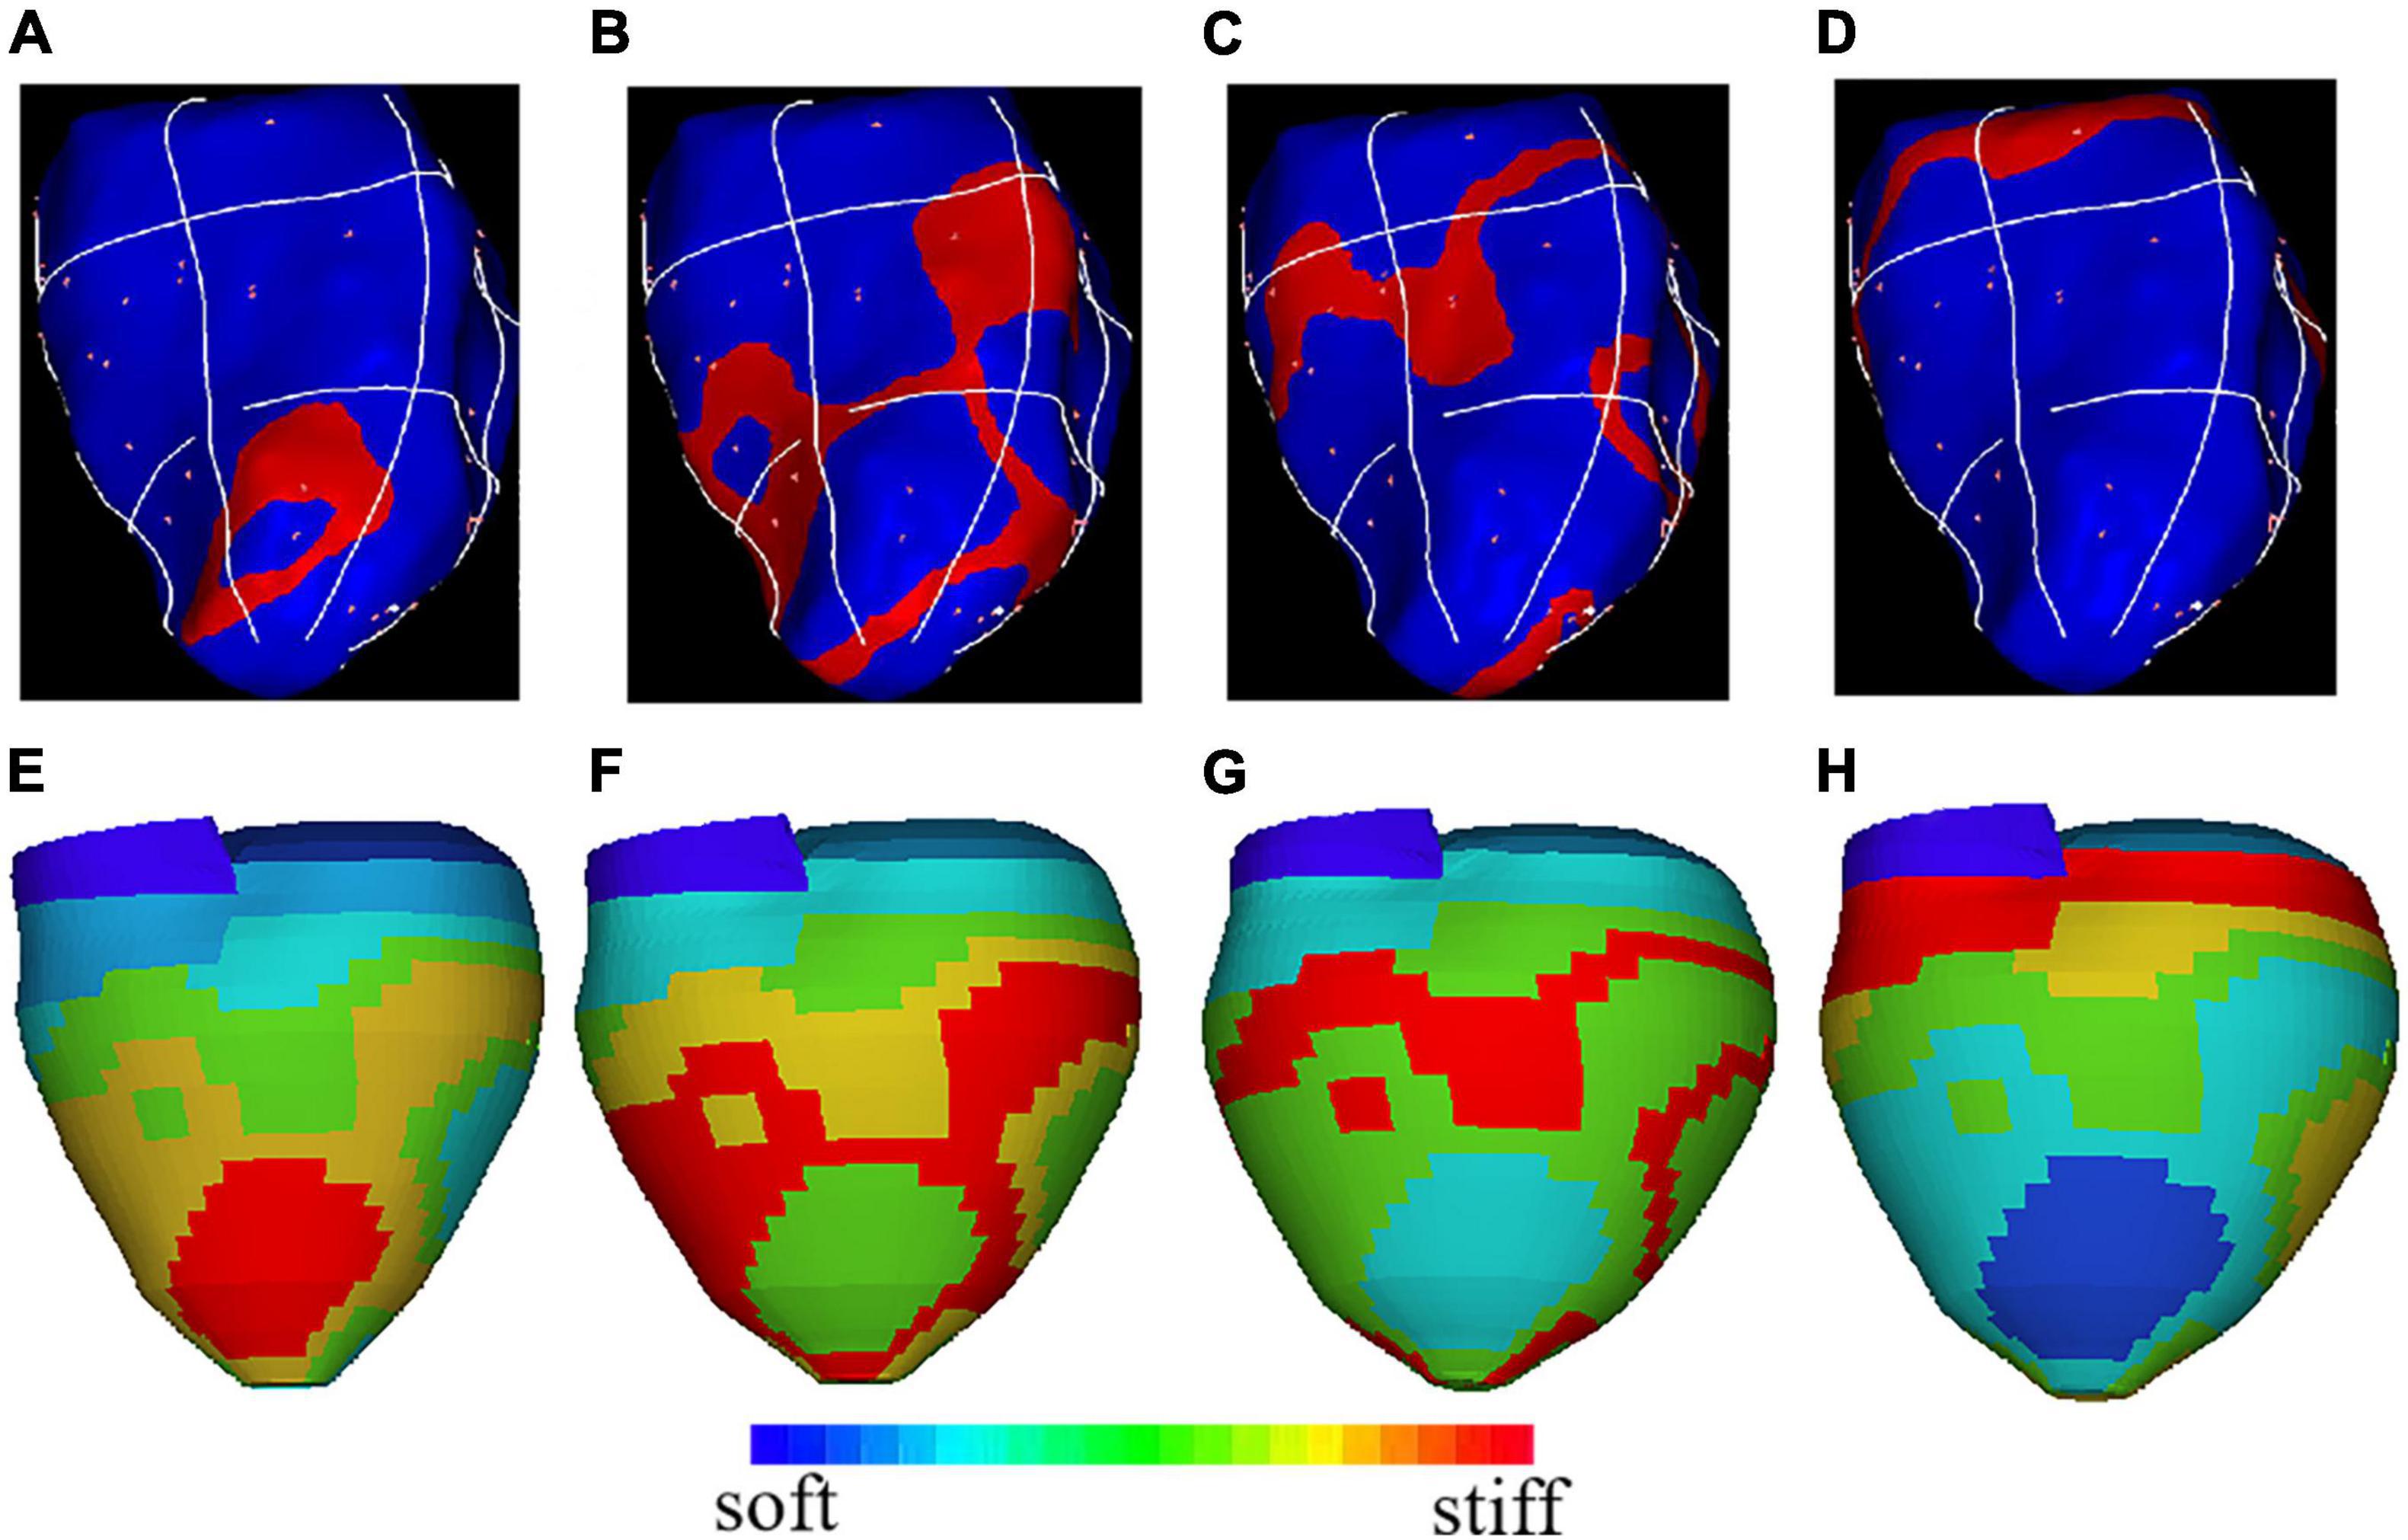

Frontiers Optimization of Left Ventricle Pace Maker Location Using Echo-Based Fluid-Structure Interaction Models